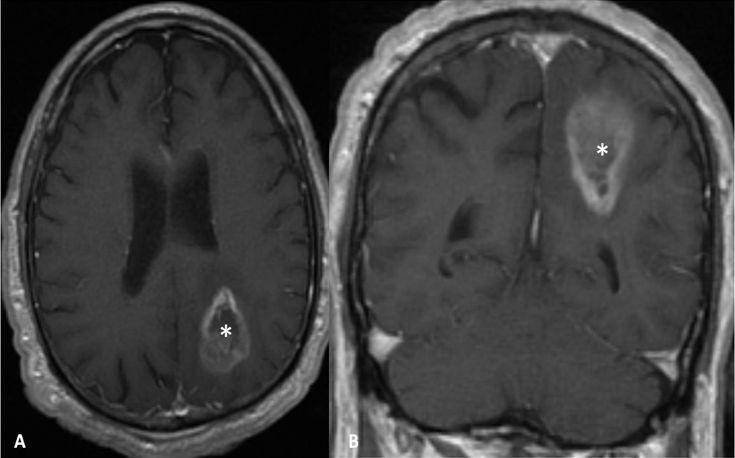

The current study evaluated the rate of ependymal enhancement and whether its presence influences survival of patients with malignant glioma (GBM).

A retrospective review of all patients who were treated in our institution from 2005 to 2011 was conducted. Data extracted from the medical records included age, date of diagnosis, co-morbidities, treatment regimen, and time of death. Magnetic resonance images (MRI) were evaluated for the presence of ependymal enhancement and its extent, and the correlation to survival was investigated.

Between 2005 and 2011, 230 patients were treated for GBM. Eighty-nine patients were excluded from the study due to insufficient data, leaving 141 patients for analysis. Median age at diagnosis was 60 years. Sixty-seven (40.6%) patients had evidence of ependymal enhancement on MRI (group A), and 70 (42.4%) patients did not have evidence of enhancement. The assessment of ependymal enhancement was inconclusive due to mass effect and ventricular compression that precluded accurate assessment for 28 (17%) patients (group C). Median survival was 14 months for group A (range, 12-16 months), 15.9 months for group B (range, 14.28-17.65 months), and 11.7 months for group C (range, 6.47-16.92 months) (P>0.05). A multivariate analysis to predict survival indicated that male gender (P=0.039), hypertension (P=0.012), and biopsy only compared to complete gross tumor resection (P=0.001) were significant for poor survival.

Pretreatment ependymal enhancement on MRI was not found to be associated with poorer survival. These results might be due to better treatments options compared to prior reports.

本研究评估了室管膜强化率及其存在是否会影响恶性胶质瘤(胶质母细胞瘤,GBM)患者的生存率。

对2005年至2011年在本机构接受治疗的所有患者进行回顾性研究。从病历中提取的数据包括年龄、诊断日期、合并症、治疗方案和死亡时间。评估磁共振成像(MRI)是否存在室管膜强化及其程度,并研究其与生存率的相关性。

2005年至2011年期间,230例患者接受了GBM治疗。由于数据不足,89例患者被排除在研究之外,剩余141例患者进行分析。诊断时的中位年龄为60岁。67例(40.6%)患者在MRI上有室管膜强化证据(A组),70例(42.4%)患者没有强化证据。由于肿块效应和脑室受压,28例(17%)患者的室管膜强化评估结果不明确(C组)。A组的中位生存期为14个月(范围为12 - 16个月),B组为15.9个月(范围为14.28 - 17.65个月),C组为11.7个月(范围为6.47 - 16.92个月)(P>0.05)。一项预测生存率的多因素分析表明,男性(P = 0.039)、高血压(P = 0.012)以及仅进行活检与完全切除肿瘤肉眼可见部分相比(P = 0.001)与生存率低显著相关。

未发现MRI上的治疗前室管膜强化与较差的生存率相关。这些结果可能是由于与先前报告相比有更好的治疗选择。